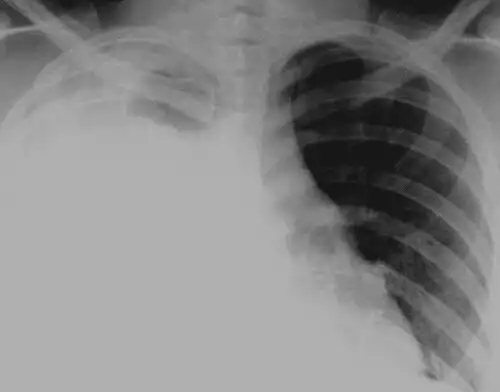

آب جنبی. آبجنبی* یا هیدروتوراکس ( به انگلیسی: Hydrothorax ) * تراکم نابهنجار مایع آبگون ( serous fluid ) در حفرۀ جنب است. این وضعیت اغلب ثانویه به نارسایی احتقانی قلب، به دنبال افزایش فشار هیدرواستاتیک درون ریه ها است. به ندرت، هیدروتوراکس می تواند در بیماران مبتلا به سیروز یا آسیت ایجاد شود. هیدرواتورکس کبدی، در مراحل پیشرفته و نهایی بیماری اغلب به درمان پاسخ نمی دهد. اگر مایع داخل حفره جنب چرکی باشد آن را پیوتوراکس، اگر خونی باشد هموتوراکس و اگر لنف باشد کیلوتوراکس می نامند.

اگرچه مکانیسم های دقیق درگیر در ایجاد هیدروتوراکس کبدی به طور کامل شناخته نشده است، اما احتمالاً از عبور آسیت از حفره صفاقی به حفره پلور از طریق نقص های کوچک دیافراگم ناشی می شود. این عیوب معمولاً کمتر از 1 سانتی متر هستند ( و ممکن است میکروسکوپی باشند ) و عموماً در قسمت تاندونی دیافراگم قرار دارند. هیدروتوراکس کبدی زمانی آشکار می شود که ظرفیت جذب فضای پلور بیشتر شود. مکانیسم های پاتولوژیک پشت تشکیل آسیت به تفصیل در جای دیگری مورد بحث قرار گرفته است